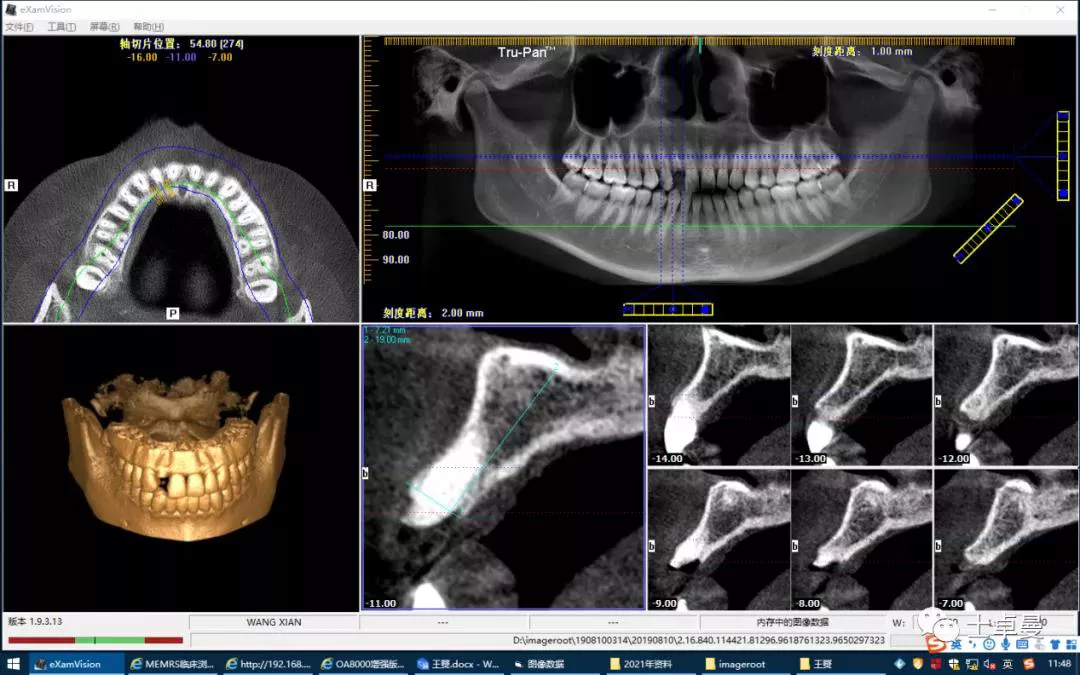

·        CBCT 检查

·       12 断根,根尖区剩余骨高度充足,可用骨高度19mm,骨宽度7.2mm。

术前根尖区显示12折裂

术前 CBCT

·        CBCT显示种植体三维位置良好;

术后 CBCT 显示种植体三维位置良好